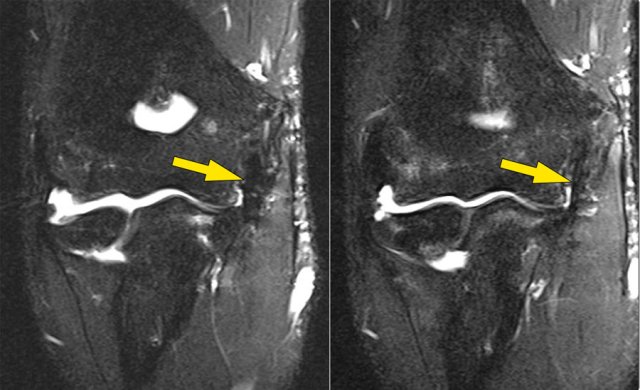

This is a 18 year old baseball pitcher with medial elbow pain.

A partial tear is seen creating a 'T-sign'.

First study the coronal T2-fatsat images and then continue reading...

Notice that the anterior bundle is intact and firmly attaches to the sublime tubercle (yellow arrow).

On the next two images there is some soft tissue edema and more abnormal signal posteriorly (red arrow). So we suspect pathology of the posterior bundle.

Now you remember that the axial images can be helpful.

So continue with the axial image.

On the axial image we nicely see the anterior bundle is o.k. (red arrow).

There is only some edema next to it.

However the posterior bundle is not o.k.

This is partial tearing.

We see this occasionally in throwing athletes, where the anterior bundle is intact and their elbow is not unstable.

They somehow have torn their posterior bundle, which causes pain.

They do not need surgery, but it still may keep them out of the game for quite a while.